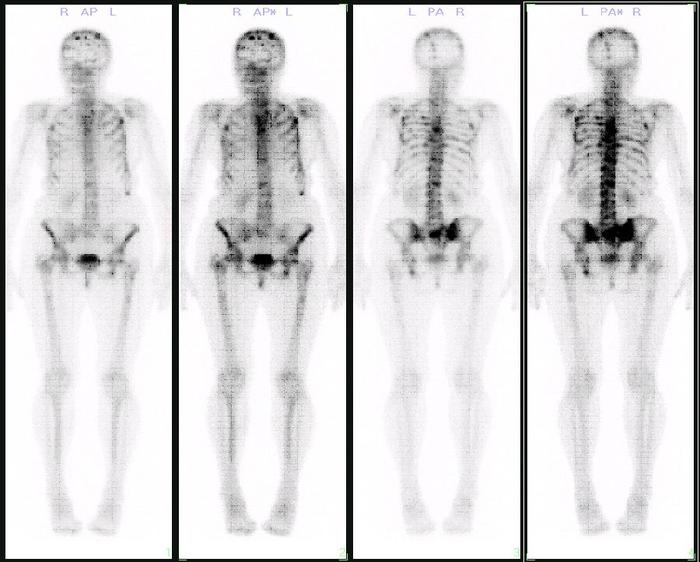

肺癌最常见的转移脏器分别是:肺、骨、脑、肝、肾上腺。进行骨扫描检查是判断肺癌骨转移的常规检查,这是是筛查骨转移的首选方式,特别是对于无临床症状的可疑骨转移,具有灵敏度高、全身一次成像、不易漏诊的优点;缺点是可能看不清,或者受其他骨关节疾病影响不好判断,需要结合其他检查进一步确诊。当骨扫描检查提示单处骨可疑转移时,我们建议对可疑部位进行X线摄影、MRI或CT检查,进一步验证。